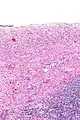

| Ovarian serous cystadenoma. The cystic space is at the top of the image. Ovarian parenchyma is seen at the bottom right. H&E stain. | |

Serous cystadenomas are diagnosed by histomorphologic examination, by pathologists. Grossly, they are, usually, small unilocular cysts that contain clear, straw-coloured fluid. However, they may sometimes be multilocular. Microscopically, the cyst lining consists of a simple epithelium, whose cells may be either:[4]

- be columnar and tall and contain cilia, resembling normal tubal epithelium

- be cuboidal and have no cilia, resembling ovarian surface epithelium